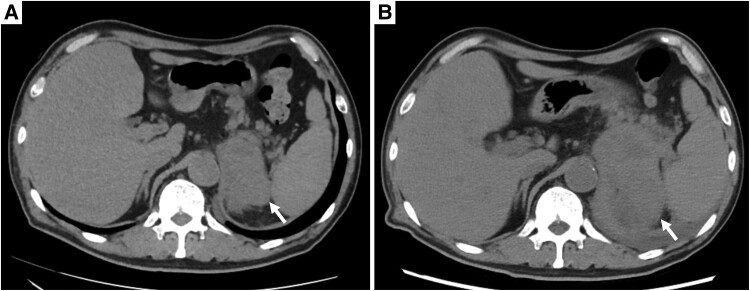

原发性恶性淋巴瘤起源于肾上腺,尤其是起源于t细胞,是非常罕见的。我们报告一例原发性单侧肾上腺间变性大细胞淋巴瘤。一名64岁的日本男性最初表现为疲劳和食欲不振。计算机断层成像显示单侧肾上腺肿块伴多器官侵犯,对肾上腺癌的鉴别提出了挑战。对右外侧股肌转移部位进行活检,免疫组化显示肿瘤细胞CD30和CD56呈阳性,CD3、CD15、CD20、CD43、穿孔素、颗粒酶B、上皮膜抗原和间变性淋巴瘤激酶呈阴性。最终,患者被诊断为原发性单侧肾上腺间变性大细胞淋巴瘤。虽然他对化疗取得了完全缓解,但在完全缓解后4个月,他因胆囊炎和淋巴瘤复发而死亡。

Primary malignant lymphomas originating in the adrenal gland, particularly of T-cell origin, are extremely rare. Here we present the primary unilateral adrenal anaplastic large cell lymphoma case. A 64-year-old Japanese male initially presented with fatigue and appetite loss. Computed tomography imaging revealed a unilateral adrenal mass with multiorgan invasion, posing challenges in differentiation from adrenal carcinoma. A biopsy from the metastatic site in the right lateral vastus muscle was obtained, and immunohistochemistry revealed that tumor cells were positive for CD30 and CD56 and negative for CD3, CD15, CD20, CD43, perforin, granzyme B, epithelial membrane antigen, and anaplastic lymphoma kinase. Ultimately, the patient was diagnosed with primary unilateral adrenal anaplastic large cell lymphoma. Although he achieved complete response to chemotherapy, he died 4 months after complete response due to cholecystitis and lymphoma recurrence.